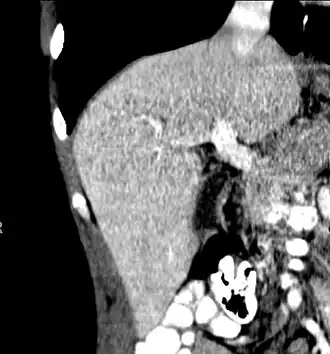

-

Axial CT image showing anomalous hepatic veins coursing on the liver's subcapsular anterior surface[74]

Maximum intensity projection (MIP) CT image as viewed anteriorly showing the anomalous hepatic veins coursing on the anterior surface of the liver

Lateral MIP view in the same patient as previous image

A CT scan in which the liver and portal vein are shown